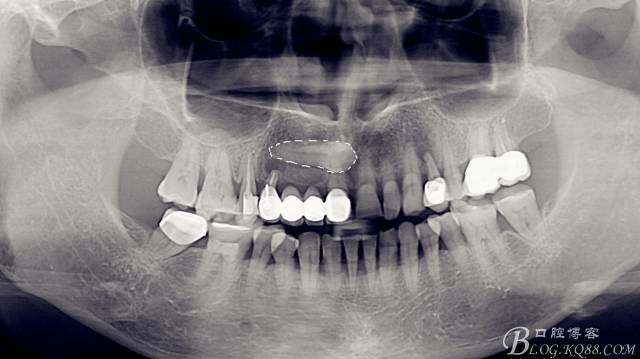

術(shù)前

全景片,此時此刻已經(jīng)拔除了A4,搔刮牙槽窩去除了囊腫。

CBCT檢查:A1和A4根尖區(qū)有一水平橫置多生牙,多生牙會影響A1到A4區(qū)域的種植手術(shù),建議外科手術(shù)拔除多生牙。